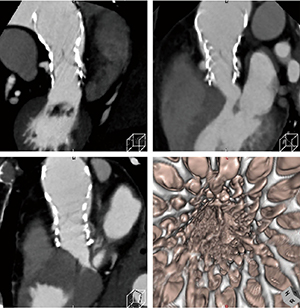

図2 冠動脈と下肢動脈造影CT(低造影剤量でIQonスペクトラルCTの仮想単色X線画像をZiostation2で画像処理) |

Ziostation2では、IQonスペクトラルCTの画像データを取り込み、VR作成やPhyZiodynamicsによる画像解析を行っている。IQonスペクトラルCTでは、Dual EnergyデータをセットにしたSBI(Spectral Based Image)が生成されるが、このデータは専用ワークステーションでしか扱えない。しかし、CT値の定義づけをしたピクセル画像を書き出すことは可能で、このデータをZiostation2に取り込むことでさまざまな処理が可能になる。これによって、仮想単色X線の低keV画像で造影効果を上げた画像を利用して、PhyZiodynamicsを適用して弁留置後のアーチファクトを除去した画像作成などが可能になる。佐々木部長は、IQonスペクトラルCTとZiostation2の組み合わせについて、「Dual Energyの画像を使い慣れたワークステーションで処理できることが一つのメリットです。IQonスペクトラルCTでは心筋評価やSBIのデータを活用した造影剤低減などが可能になっています。最終的にはDual Energyによって精度の高い冠動脈評価が行えるように検討を進めていきます」と述べる。